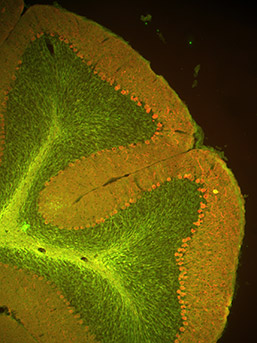

Questa sezione di cervelletto di topo adulto mostra i recettori dell'insulina (verde) e della calbindina (rosso), che in questo caso è presente nei neuroni cerebellari chiamati cellule di Purkinje. I recettori dell'insulina sono altamente espressi nelle fibre che formano le sinapsi sulle cellule di Purkinje, che esprimono MHCI. Così sia nel cervelletto che nell'ippocampo (immagine precedente), i recettori dell'insulina sono altamente espressi nelle cellule che formano sinapsi sui neuroni che esprimono MHCI, il che suggerisce che la MHCI e i recettori dell'insulina potrebbero interagire, direttamente o indirettamente, nel cervello vivente. (Immagine: Lisa Boulanger)